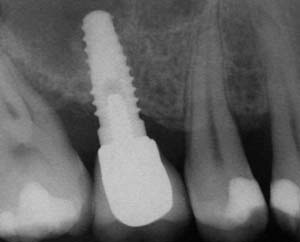

A 55-year-old male was referred for implant placement and prosthetic rehabilitation in the area of tooth No. 15. The tooth had been extracted 4 years prior. The radiograph revealed inadequate bone height for implant positioning (Figure 6). It was decided to insert an implant that was 11.5 mm in length and 3.75 mm in diameter, performing a slight osteotomic maxillary sinus lift. A heterologous bone graft also was planned to obtain a larger sinus lift.

A full-thickness mucoperiosteal flap was raised, and alternating osteotomes were used to prepare the implant site. After achieving a length of 7 mm (Figure 7A and Figure 7B), heterologous bone graft was implanted and the osteotome sequence was repeated. The implant showed primary stability.

Second-stage surgery was performed after 4 months (Figure 8); healing abutments were placed and the soft tissue was allowed to heal for 5 more weeks. Then, splinted porcelain-fused-metal (PFM) crowns supported by custom gold abutments were delivered (Figure 9 and Figure 10).

Figure 8 At 4 months after treatment, the radiograph revealed the presence of a bone layer surrounding the implant.